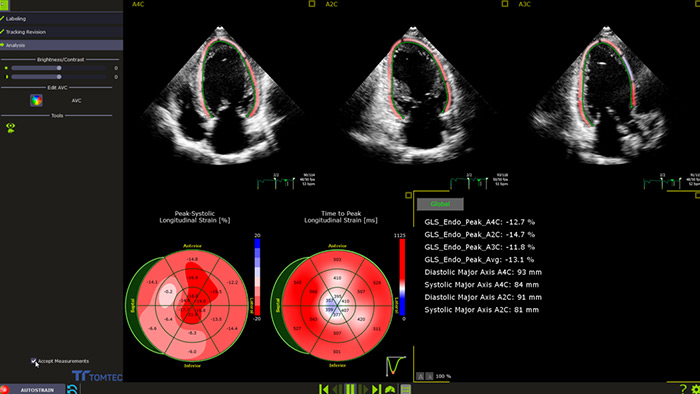

Toutefois, l'évaluation simple et largement disponible de la fraction d'éjection ventriculaire gauche (FEVG) par échochardiographie 2D ne permet souvent pas de détecter les petites modifications de la contractilité du VG. Des mesures plus précises sont disponibles en effectuant une FE volumique 3D. Mais c'est la déformation longitudinale globale (GLS) qui complète l'une ou l'autre analyse, en tant que paramètre de déformation longitudinale pour la détection précoce d'un dysfonctionnement subclinique du VG.4

Mesure automatisée des GLS pour un usage clinique en routine

Sur l'échographe ou pour le post-traitement, AutoStrain offre une solution GLS simple et rapide, pilotée par la reconnaissance automatique des vues et le placement automatique des contours. Un algorithme éprouvé sur plus de 6000 images pour assurer sa robustesse, AutoStrain VG fournit une mesure reproductible de la déformation du ventricule gauche par simple pression sur un bouton, pour une utilisation clinique quotidienne.

La quantification de la fonction cardiaque pour gagner en confiance Philips Dynamic HeartModelA.I. est un outil 3D qui fournit une fraction d'éjection (FE) robuste et reproductible en quelques secondes dans le cadre d'un flux de travail de routine.